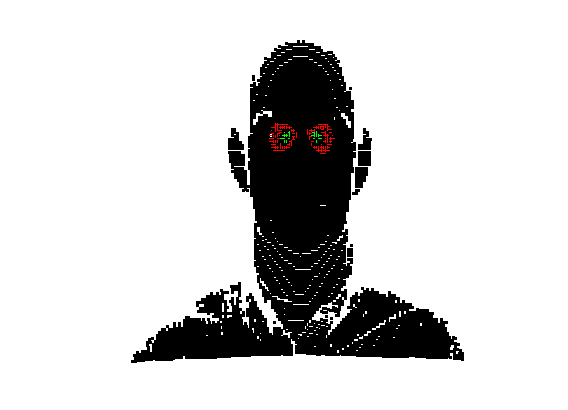

The landmarking system that we have implemented is a modified version of Creusot et al [23], where landmark candidates are generated via per-landmark scoring functions and then a configural model is iteratively fitted using a sample-consensus scheme. There are two parts to this algorithm: an off-line training scheme, shown in Fig. 5 and an online landmarking scheme, shown in 6. Note that we consider a sparse model of the face to consist of a set of landmarks in paticular configuration along with a set of landmark detector functions that score the likelihood of a particular vertex being a particular landmark, based on its local shape.

Referring to Fig. 5, our method is a supervised learning technique - landmarks are marked by hand on a set of training images. We used 279 faces (each different individuals) in the Face Recognition Grand Challenge (FRGC) dataset [26]. The landmarks used are described in table 1 111Some descriptions taken from www.facebase.org and can be seen on an example FRGC 3D face scan in Fig. 7.

Fig. 9 shows examples of the fitted model (trained on FRGC data) on the first four subjects in our Headspace training set. Note that the mean of the landmarks in the sparse model is centred on the orgin, and so the scan data is moved towards that and becomes frontal in pose. We note that other researchers [28] have used 3D landmark localisation to find the head, but often this only includes landmarks that are relatively easy to localise, namely inner eye corners and nose. Localising more landmarks over a wider facial area has a number of advantage in terms of cropping, pose normalisation and global 3D template warping, all of which are described later.